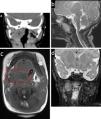

Caso clínicoRecién nacida a término que presentó dificultad respiratoria desde el nacimiento y requirió ventilación mecánica. La tomografía computarizada (TC) y la resonancia magnética (RM) realizadas con 11 días de vida mostraron una masa centrada en la orofaringe y con extensión al espacio parafaríngeo con morfología e intensidad de señal similares a las del cerebro, sin comunicación con el sistema nervioso central, lo que sugirió un coristoma neuroglial (fig. 1). Fue sometida a una resección parcial por vía oral para recoger material para anatomía patológica, la cual mostró tejido glial positivo para S100 y proteína ácida fibrilar glial, lo que confirmó el diagnóstico de coristoma neuroglial (fig. 2).

Tomografía computarizada facial sin contraste en el plano coronal, perpendicular al paladar duro (a) y resonancia magnética del cuello en secuencias sagital T2 (b), axial T1 (c) y coronal STIR (d). Se observa la integridad de las estructuras óseas en la base del cráneo (1). Hay una masa (2 y círculo rojo) centrada en la orofaringe con extensión al espacio parafaríngeo derecho (compárese con el espacio contralateral, (3). Nótese la reducción de la cavidad oral (4) y la permeabilidad orofaríngea (la masa llega hasta el cuerpo de la lengua, (5), y el aspecto cerebral de la masa con una morfología que se asemeja a circunvoluciones corticales, sustancia gris hipointensa y sustancia blanca amielínica hiperintensa en secuencia STIR (d).